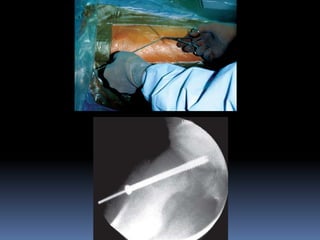

 INSITU PIN OR SCREW FIXATION –

Percutaneous in situ pinning most often used treatment in mild , moderate

& some severe acute or chronic slip.

Open insitu pinning – more severe acute or acute on chronic slip.

Use of single larger diameter central pin or screw is recommended –

technically simpler.

Use of pediatric cannulated screws over guide wire – easier & more

accurate.

Pins or screws shouldnot be removed until physis closes.

Generally two screws used for acute unstable slips & one for chronic stable

slips.

Pin tip be advanced to 8mm or one third of femoral head radius from

subchondral bone.

Pin or screw be placed in center of femoral head.

Advantage is it helps in minimizing skin incision.

Disadvantage is pin penetration, which can lead to joint sepsis, localized

acetabular erosion, synovitis, chondrolysis & late degenerativeOA.

Incidence of pin penetration – 14 to 60%

 TECHNIQUES :

 CANALE ET AL

 MORRISSY ET AL

 Morrissy et al: